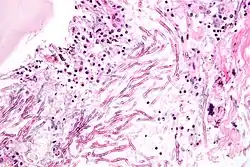

Une mycose est une infection fongique provoquée par une ou plusieurs espèces de microchampignons parasites ou saprophytes. Les pathologies fongiques étudiées par la mycologie médicale, sont souvent subdivisées en infections appelées superficielles, mycoses sous-cutanées et mycoses systémiques[1]. Elles concernent le plus souvent de petites zones de la peau et/ou des muqueuses. Beaucoup plus rarement le champignon envahit des organes internes (quand il s'agit des poumons ils peuvent y provoquer une infection évoquant une pneumonie ou une tuberculose pulmonaire).